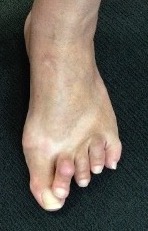

Claw Toes

Definition

Hyperextension of MTPJ

PIPJ / DIPJ flexion

Usually all toes affected